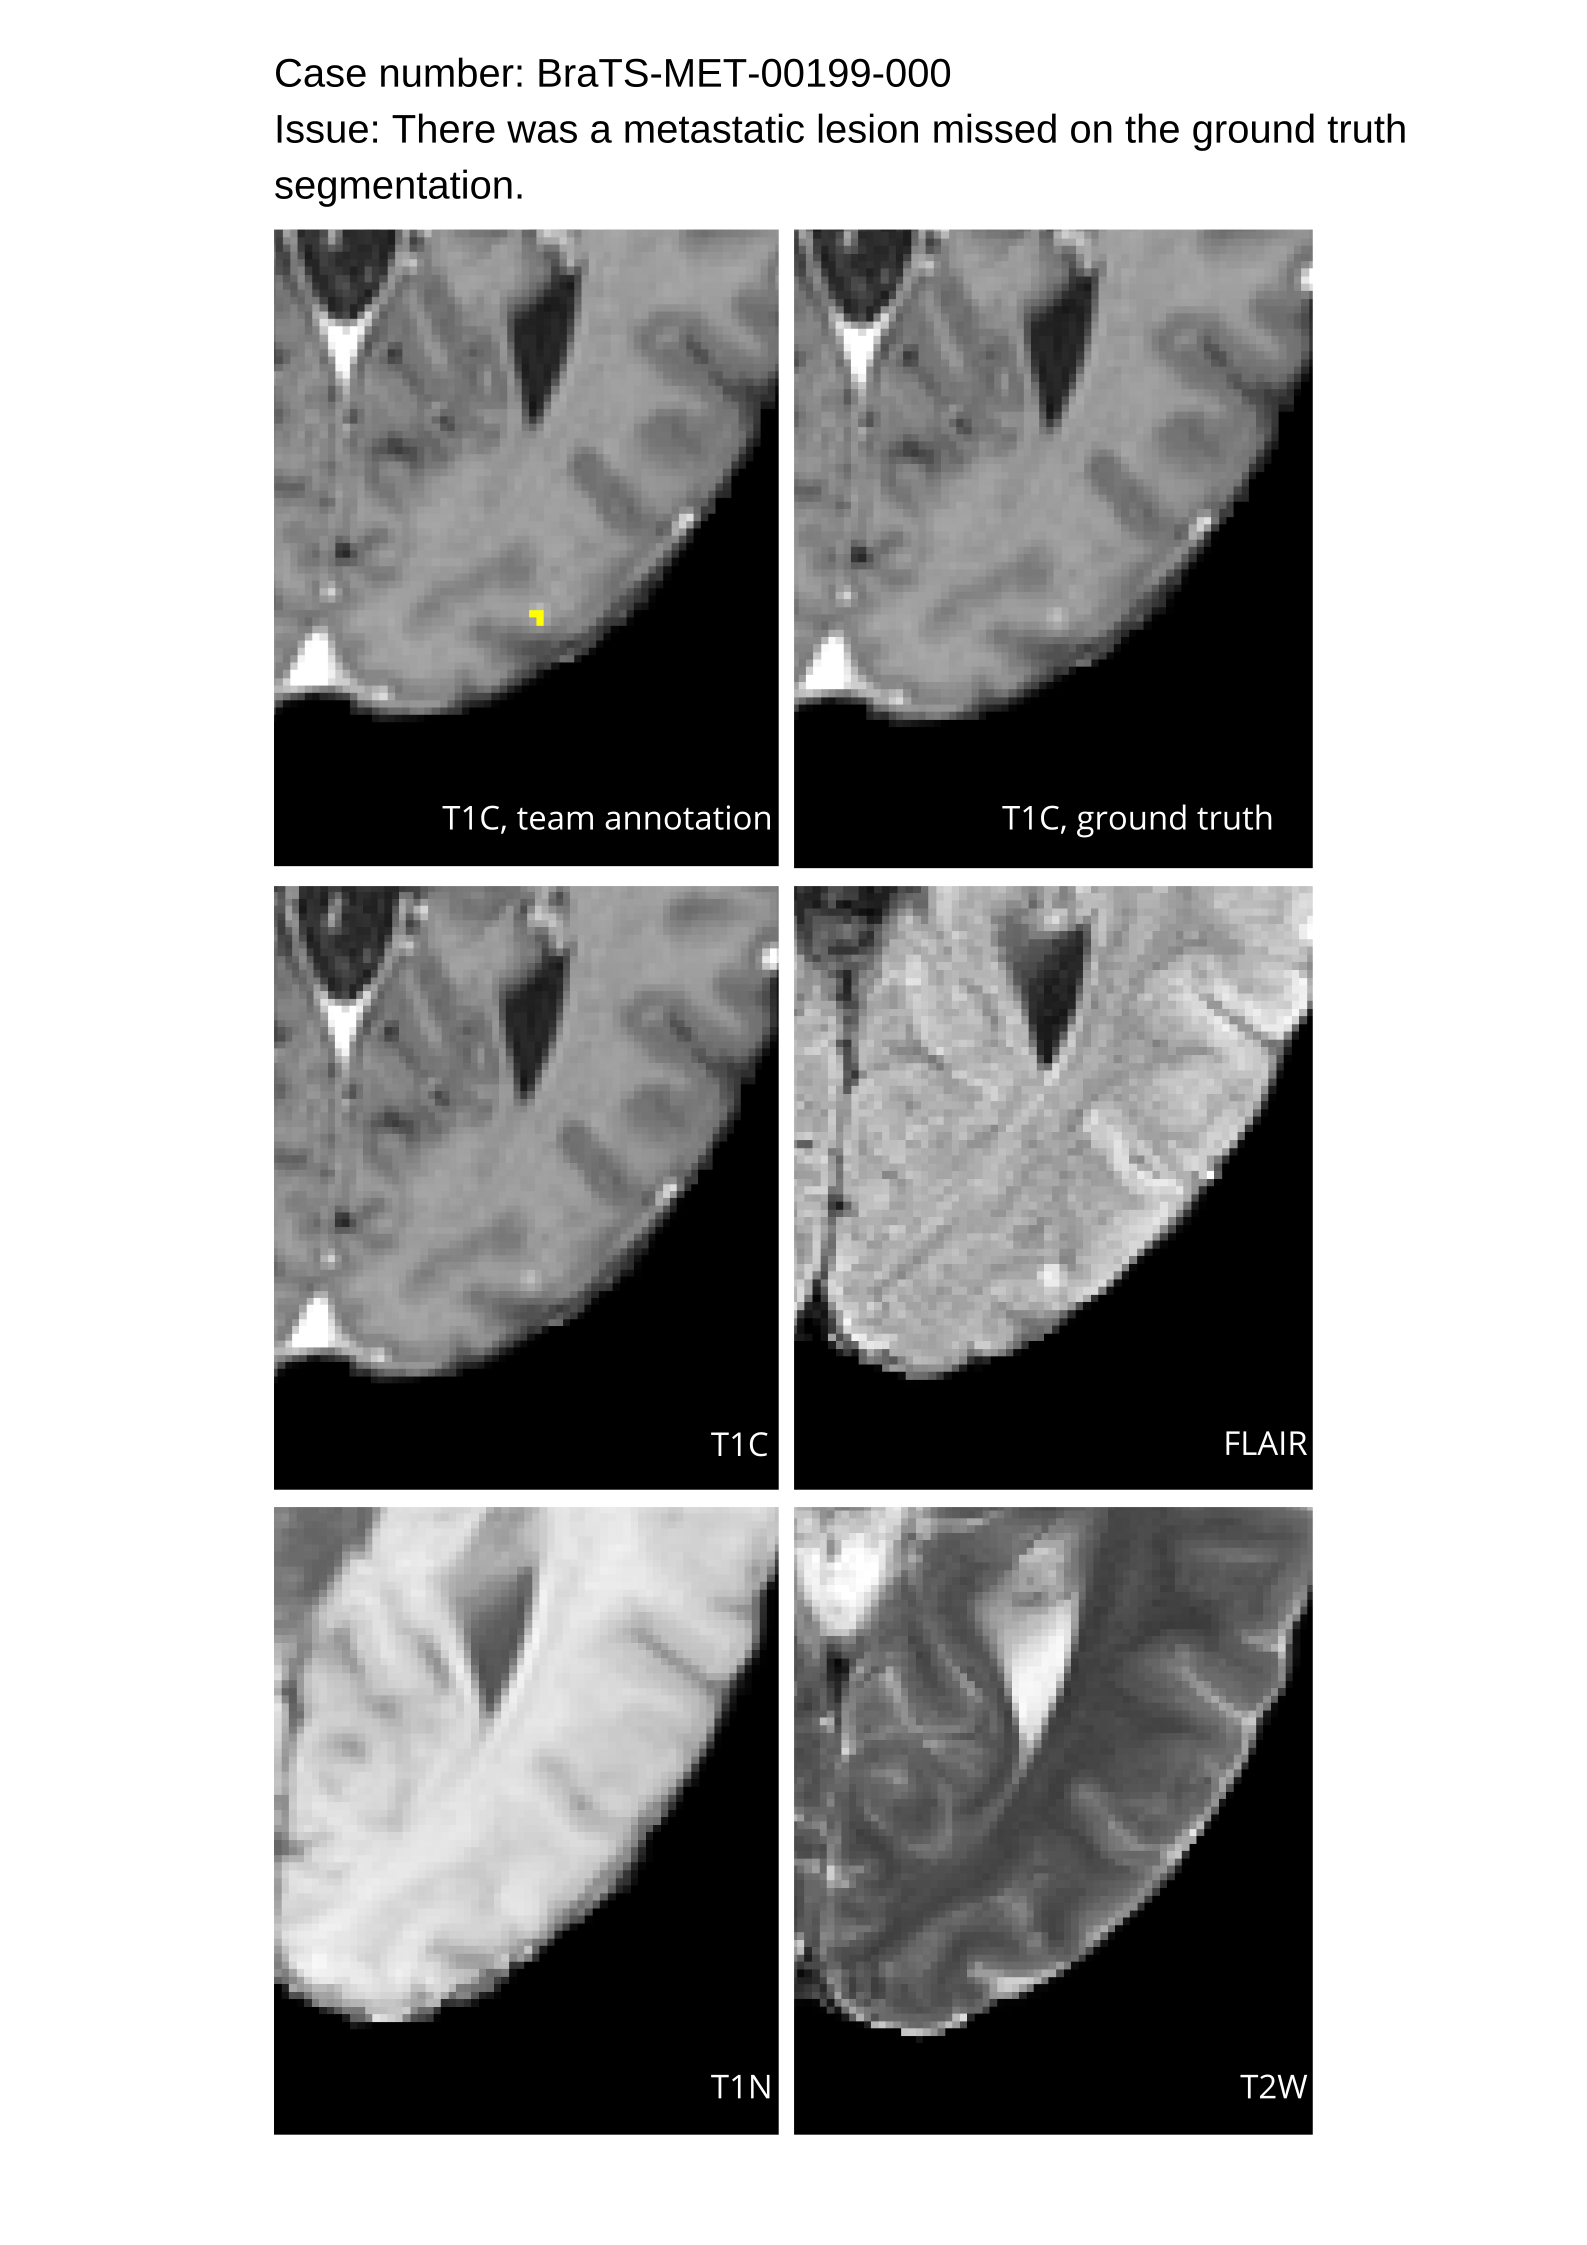

Table 4 provides the relative ranking for each team. Team NVAUTO ranked first in the challenge, with an average rank across subjects of 7.9 and a PatientWise mean of 0.38. Team SY placed second with a PatientWise mean of 0.41 across all patients. The supplementary material depicts the pitfall cases with figures illustrating the false positives or missed lesions.